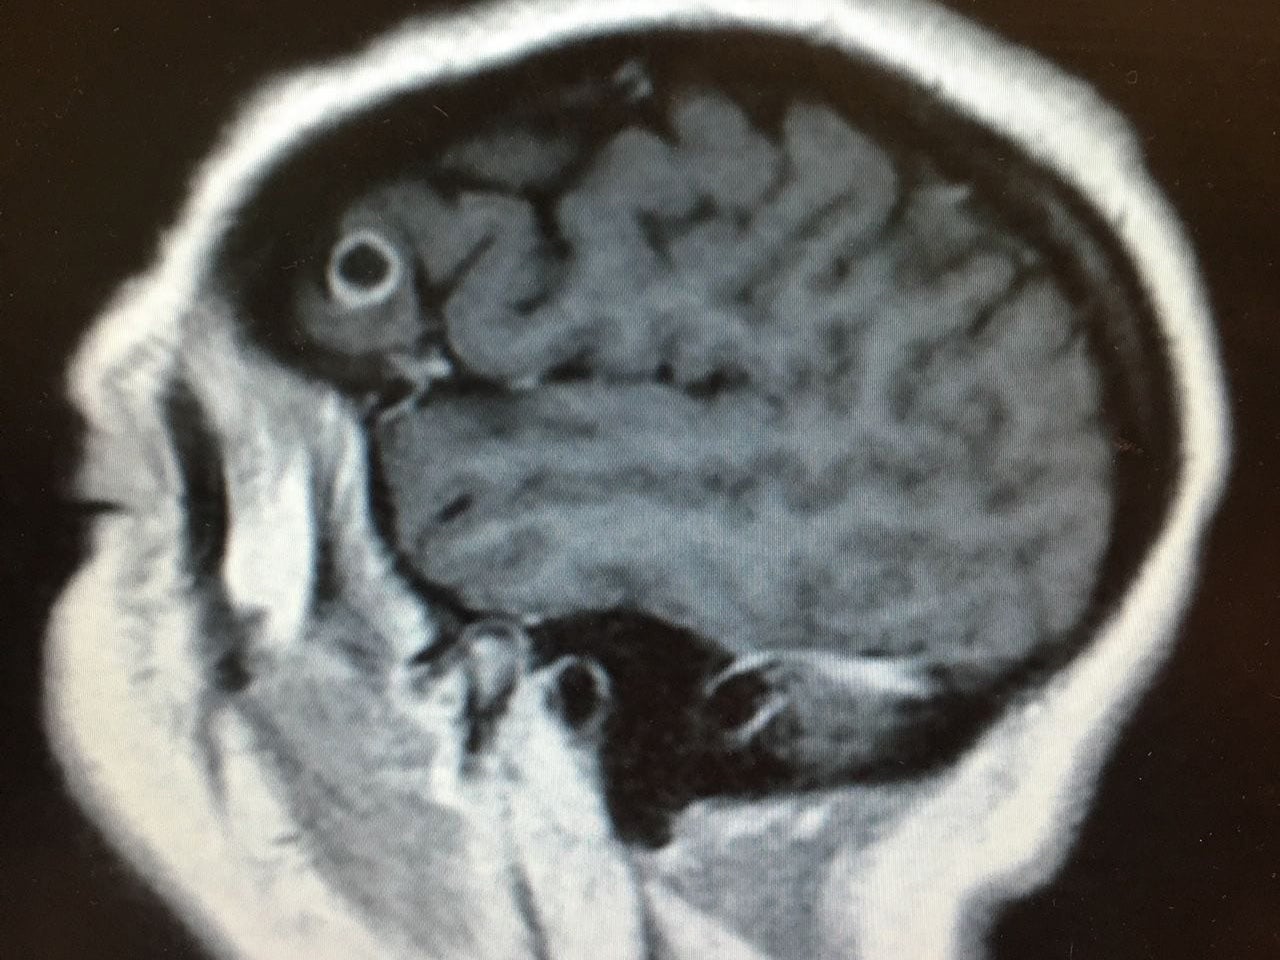

Doctors carried out an MRI scan which revealed an 8mm-long lesion in the occiptal lobe at the back of her head.

Surgeons removed what appeared to be a cyst without any complications - only to discover that it was not human tissue.